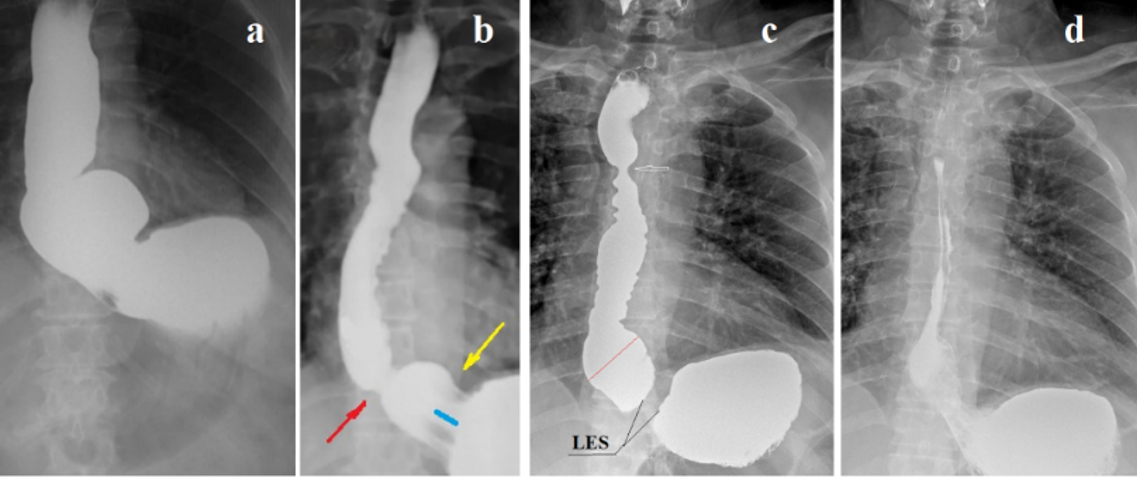

6) The results of the use of a large tablet: For several years I have been offering to swallow LT to patients with GERD symptoms and have assessed the treatment effect based on questionnaires that patients filled out before and 1-6 months after that [40]. The study involved 37 patients who had at least one of the symptoms characteristics of GERD. Patients filled in the questionnaire. They were divided into 2 groups. The first group consisted of 20 patients. They had reflux index (RI - sum of symptoms depending on severity), which is proportional to the severity of GERD, less than 10 (5.4±0.4). The average age was 30 years, and the duration of the disease ranged from 3 to 39 months. In 17 patients of the second group, RI was equal to or more than 10 (20.1 ± 1.6). The average age was 51 years, and the duration of the disease ranged from 5 to 35 years. Patients swallowed 3 tablets with a diameter of 2.0 - 2.5 cm. After 0.5 - 1 month. patients re-filled the questionnaire. Results. In patients of the 1st group after taking the tablets RI decreased to 0.6 ± 0.2 (P <0.001). The effect of treatment lasted from 1 to 7 months. In the 2nd group after swallowing the tablets RI decreased to 10.1 ± 2.8 (P <0.01). In 3 cases, there was no effect on taking the tablets. The positive effect lasted 1-3 weeks. Thus, it has shown that in young and middle-aged people, taking LT alone resulted in the disappearance of symptoms or a significant reduction in symptoms for about 6 months. In older people with a long history the treatment effect was significantly shorter, and in some patients, it was not detected at all [40]. X-ray examination using high pressure in the stomach has shown that the treatment effect depends on the degree of damage to the LES. The effect of stretching the LES was absent in some patients with the LES chalasia (Figure 4а & Figure 4b). However, stretching the aorto-esophageal sphincter (AES) was always accompanied by significant improvement, despite the incompetence of the LES (Figure 4c & Figure 4d) [30].

Figure 4. Radiographs of patients with chalasia EGJ. (a-b). A 68-year-old woman has been ill since her youth, when heartburn appeared. She was diagnosed with asthma when she was young. The bronchospasm attacks passed. A small amount of milk in coffee causes severe heartburn after 15-30 minutes. She takes 20 mg of PPI per day, which is enough to prevent heartburn. Repeated endoscopy always revealed only a “hiatal hernia.” High resolution manometry at the age of 60 years revealed low pressure of the UES and normal tone of the LES. (a). During maximum provocation, a sharp dilation of the esophagus is visible, especially in its ampullary region, as well as a sharp dilation and shortening of the esophago-gastric junction. (b). After 5 minutes, free reflux from the stomach into the esophagus is determined. She swallowed LT twice but felt no effect. (c-d). A 72-year-old man complained of a debilitating cough, change in voice, and a sensation of a foreign body in the throat for 4 months. Very rarely small pieces of food appear in the mouth. For a month he wakes up at night because he is choking on saliva. He does not feel any acid or bitterness in his mouth. He has no heartburn, pain, or dysphagia. About 15 years ago he had heartburn, which went away only after swallowing a tablet with a diameter of about 3 cm. Since then, he considered himself healthy. (с). A sharp shortening of the LES (1 cm), expansion of the esophageal ampulla and symmetrical narrowing of the esophagus at the level of the aortic arch (arrow) are detected. (d). After 5 minutes of free reflux of barium from the stomach into the esophagus is determined.

The patient swallowed a tablet with a diameter of 1.9 cm. After this, he stopped choking on saliva at night. This is a typical example of the formation of a functional sphincter over the aortic narrowing of the esophagus (AES), which was responsible for the non-esophageal symptoms. As a result of the tablet passing through this functional narrowing, the symptoms are resolved without the use of other methods.